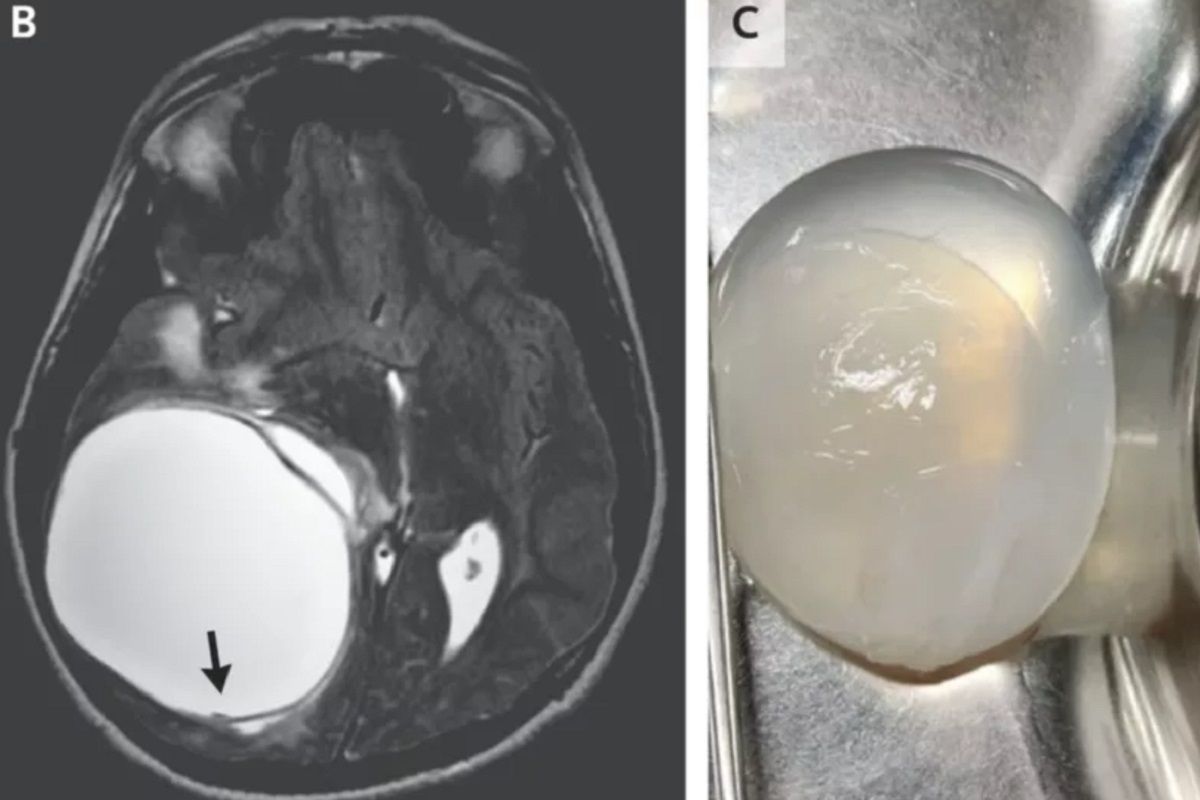

Un copil de 14 ani acuza dureri de cap și stări de vomă. Este absolut ȘOCANT ce au descoperit medicii. Mai mult de 1 milion de oameni pot fi afectați

Unui adolescent i s-a îndepărtat o creștere uriașă din creier după ce a fost infectat cu un parazit tenia (viermi). Tânărul de 14 ani, anterior… Citește mai mult »Un copil de 14 ani acuza dureri de cap și stări de vomă. Este absolut ȘOCANT ce au descoperit medicii. Mai mult de 1 milion de oameni pot fi afectați